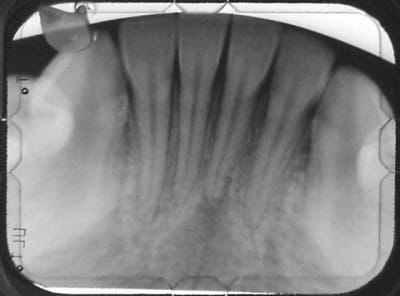

Rx. ...

resultat de pas de controle: gros arc rond

et élastiques: trop de friction

bref tout ce qu'il ne faut pas faire

Oui en effet mais c'est pas la cata , j'ai vu des cas ou il restait 3 mm de racine dans l'os.

si c'est PAS la cata,c'est dommage de traiter la 31 à 15 ans pr une mortif consecutive à des forces trop importantes